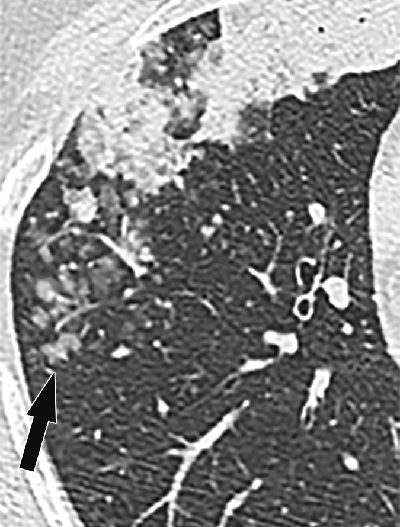

CT features that strongly suggest aerogenous spread include "persistent centrilobular nodules and branching opacities (tree-in-bud nodules), typically with ill-defined margins and ground-glass attenuation," the study team wrote. Well-defined nodules with soft-tissue attenuation are less common in this scenario.

Nodules suggestive of aerogenous spread tend to be clustered, and they always show evidence of growth on serial images, they wrote. In some cases, they progress to confluent air-space disease.

When these metastases are remote from the primary lesion, the nodules tend to have a dependent distribution in the lower lobes. The appearance on CT "reflects cancer cells lining the small airways and alveolar spaces in a lepidic pattern with variable amounts of intra-alveolar material," the authors explained.